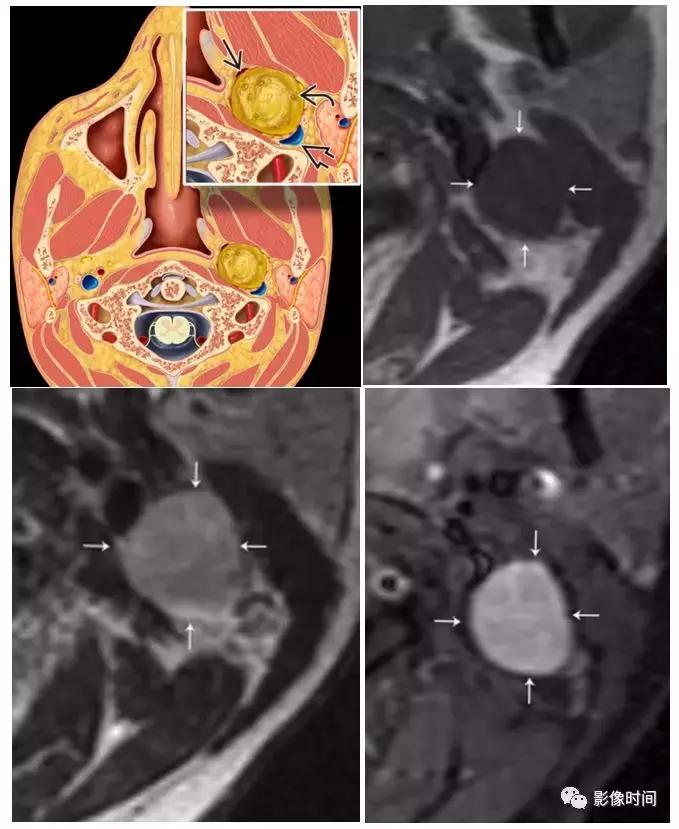

(1)神经鞘瘤:好发于 20-60 岁男性患者,除了来源于第 9-12 对颅神经,颈动脉间隙神经鞘瘤还可来源于交感神经丛。颈动脉间隙神经鞘瘤通常沿受累神经长轴走行,呈梭形或卵圆形,单发多见,部分合并囊性、非强化区,颈内动脉通常受压向前或外侧移位。

模式图显示神经鞘瘤位于颈内静脉前内侧和颈内动脉后外侧之间。T1WI 显示病灶呈稍低信号,T2WI 稍高信号,明显强化。

(2)神经纤维瘤:20-30 岁青年患者多见,10% 神经纤维瘤与发生于神经纤维瘤病,根据形态分为弥漫型、丛状、局灶型,纵向及梭形生长,特征性表现为「靶征」或「鱼眼征」,是指病灶中心的 T2WI 低信号。

T1WI 显示病灶相对于肌肉呈低信号,T2WI 病灶呈高信号,病灶包绕左侧颈内动脉 (i)。注意此病变的特征「鱼眼」或「靶」外观(黑色箭头)。